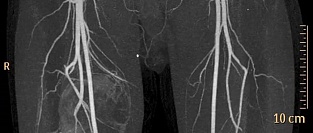

Рекомендации ESC/ ESVS по заболеваниям периферических артерий 2017

На проходившем в Барселоне (Испания) ежегодном конгрессе Европейского общества кардиологов (ESC) пре...

08.09.2017 7488 #атеросклероз #атеросклероз периферических артерий #атеросклероз сосудов нижних конечностей